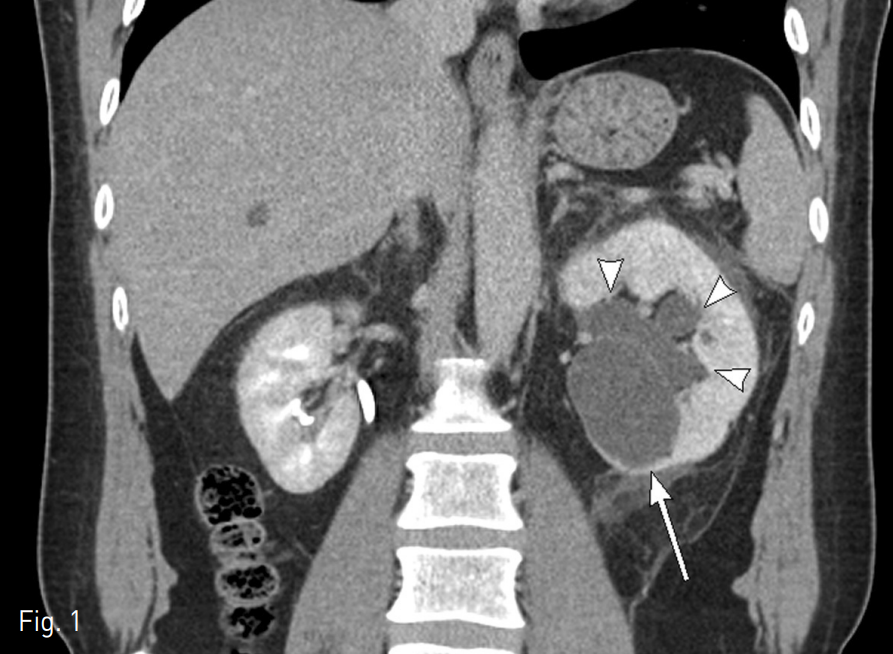

복부 CT상 좌측 신장에 약 5cm 크기의 단순낭종과 수신증이 관찰되었다. 단순낭종에 의한 요관신우연결부위 (ureteropelvic junction)의 협착으로 수신증이 발생된 것으로 생각되었고 좌측 신장에 작은 결석이 있었지만 이로 인한 수신증은 아닌 것으로 보였다 (Fig. 1).

Fig. 1

Abdominal enhanced coronal CT scan shows simple renal cyst in left kidney (arrow) and hydronephrosis (arr owhead).